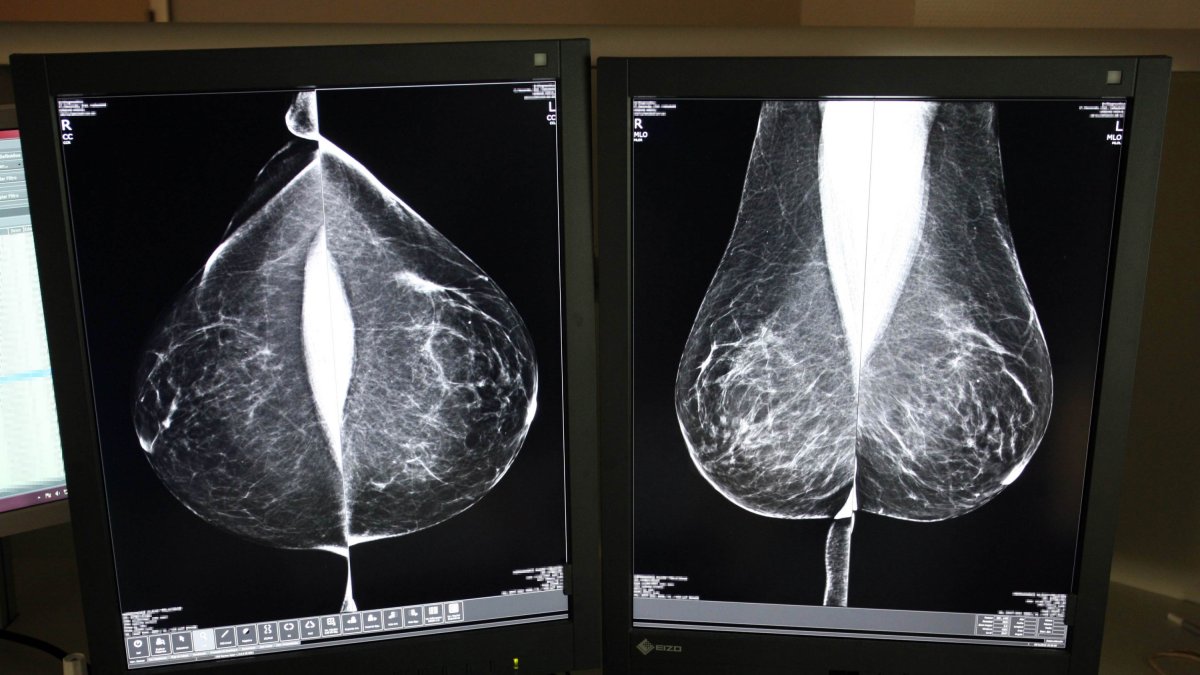

Estudio una mamografía digital, en el servicio de mamografías.